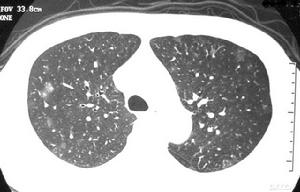

急性侵襲型肺麴黴病血常規:嗜酸性細胞升高。IgG沉澱素90%以上陽性。血清總IgE明顯升高。胸部X線表現為不同形態的肺浸潤,以支氣管肺炎最常見。多發性局灶性浸潤常分布在周圍肺野。部分病例表現類似肺栓塞或梗死。大葉肺實變和粟粒狀病變亦有所見。隨著病變進展,常常出現肺空洞,其中亦可形成急性麴黴球。並發胸腔積液時則見相應X線徵象。